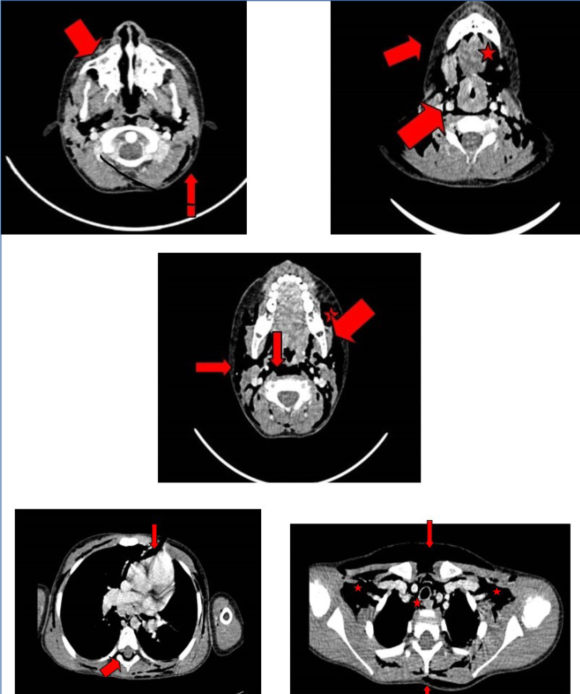

Reingresa a UCIP, se mantiene observación clínica. En las siguientes 24 horas aumento del enfisema, agrega disfagia e intenso dolor torácico. Se comienza oxigenoterapia por cánula nasal. Con planteo de lesión en vía aérea se consulta con otorrinolaringología. Se solicita tomografía de cuello y tórax con contraste que evidencia neumomediastino que asocia neumorraquis. Extenso enfisema subcutáneo con disección de planos músculo-viscerales de este último. Resto del estudio sin alteraciones (Figura 2).

Figura 2: TAC donde se evidencia el aire disecando los diferentes espacios. Se puede visualizar neumomediastino y neumorraquis asociado.